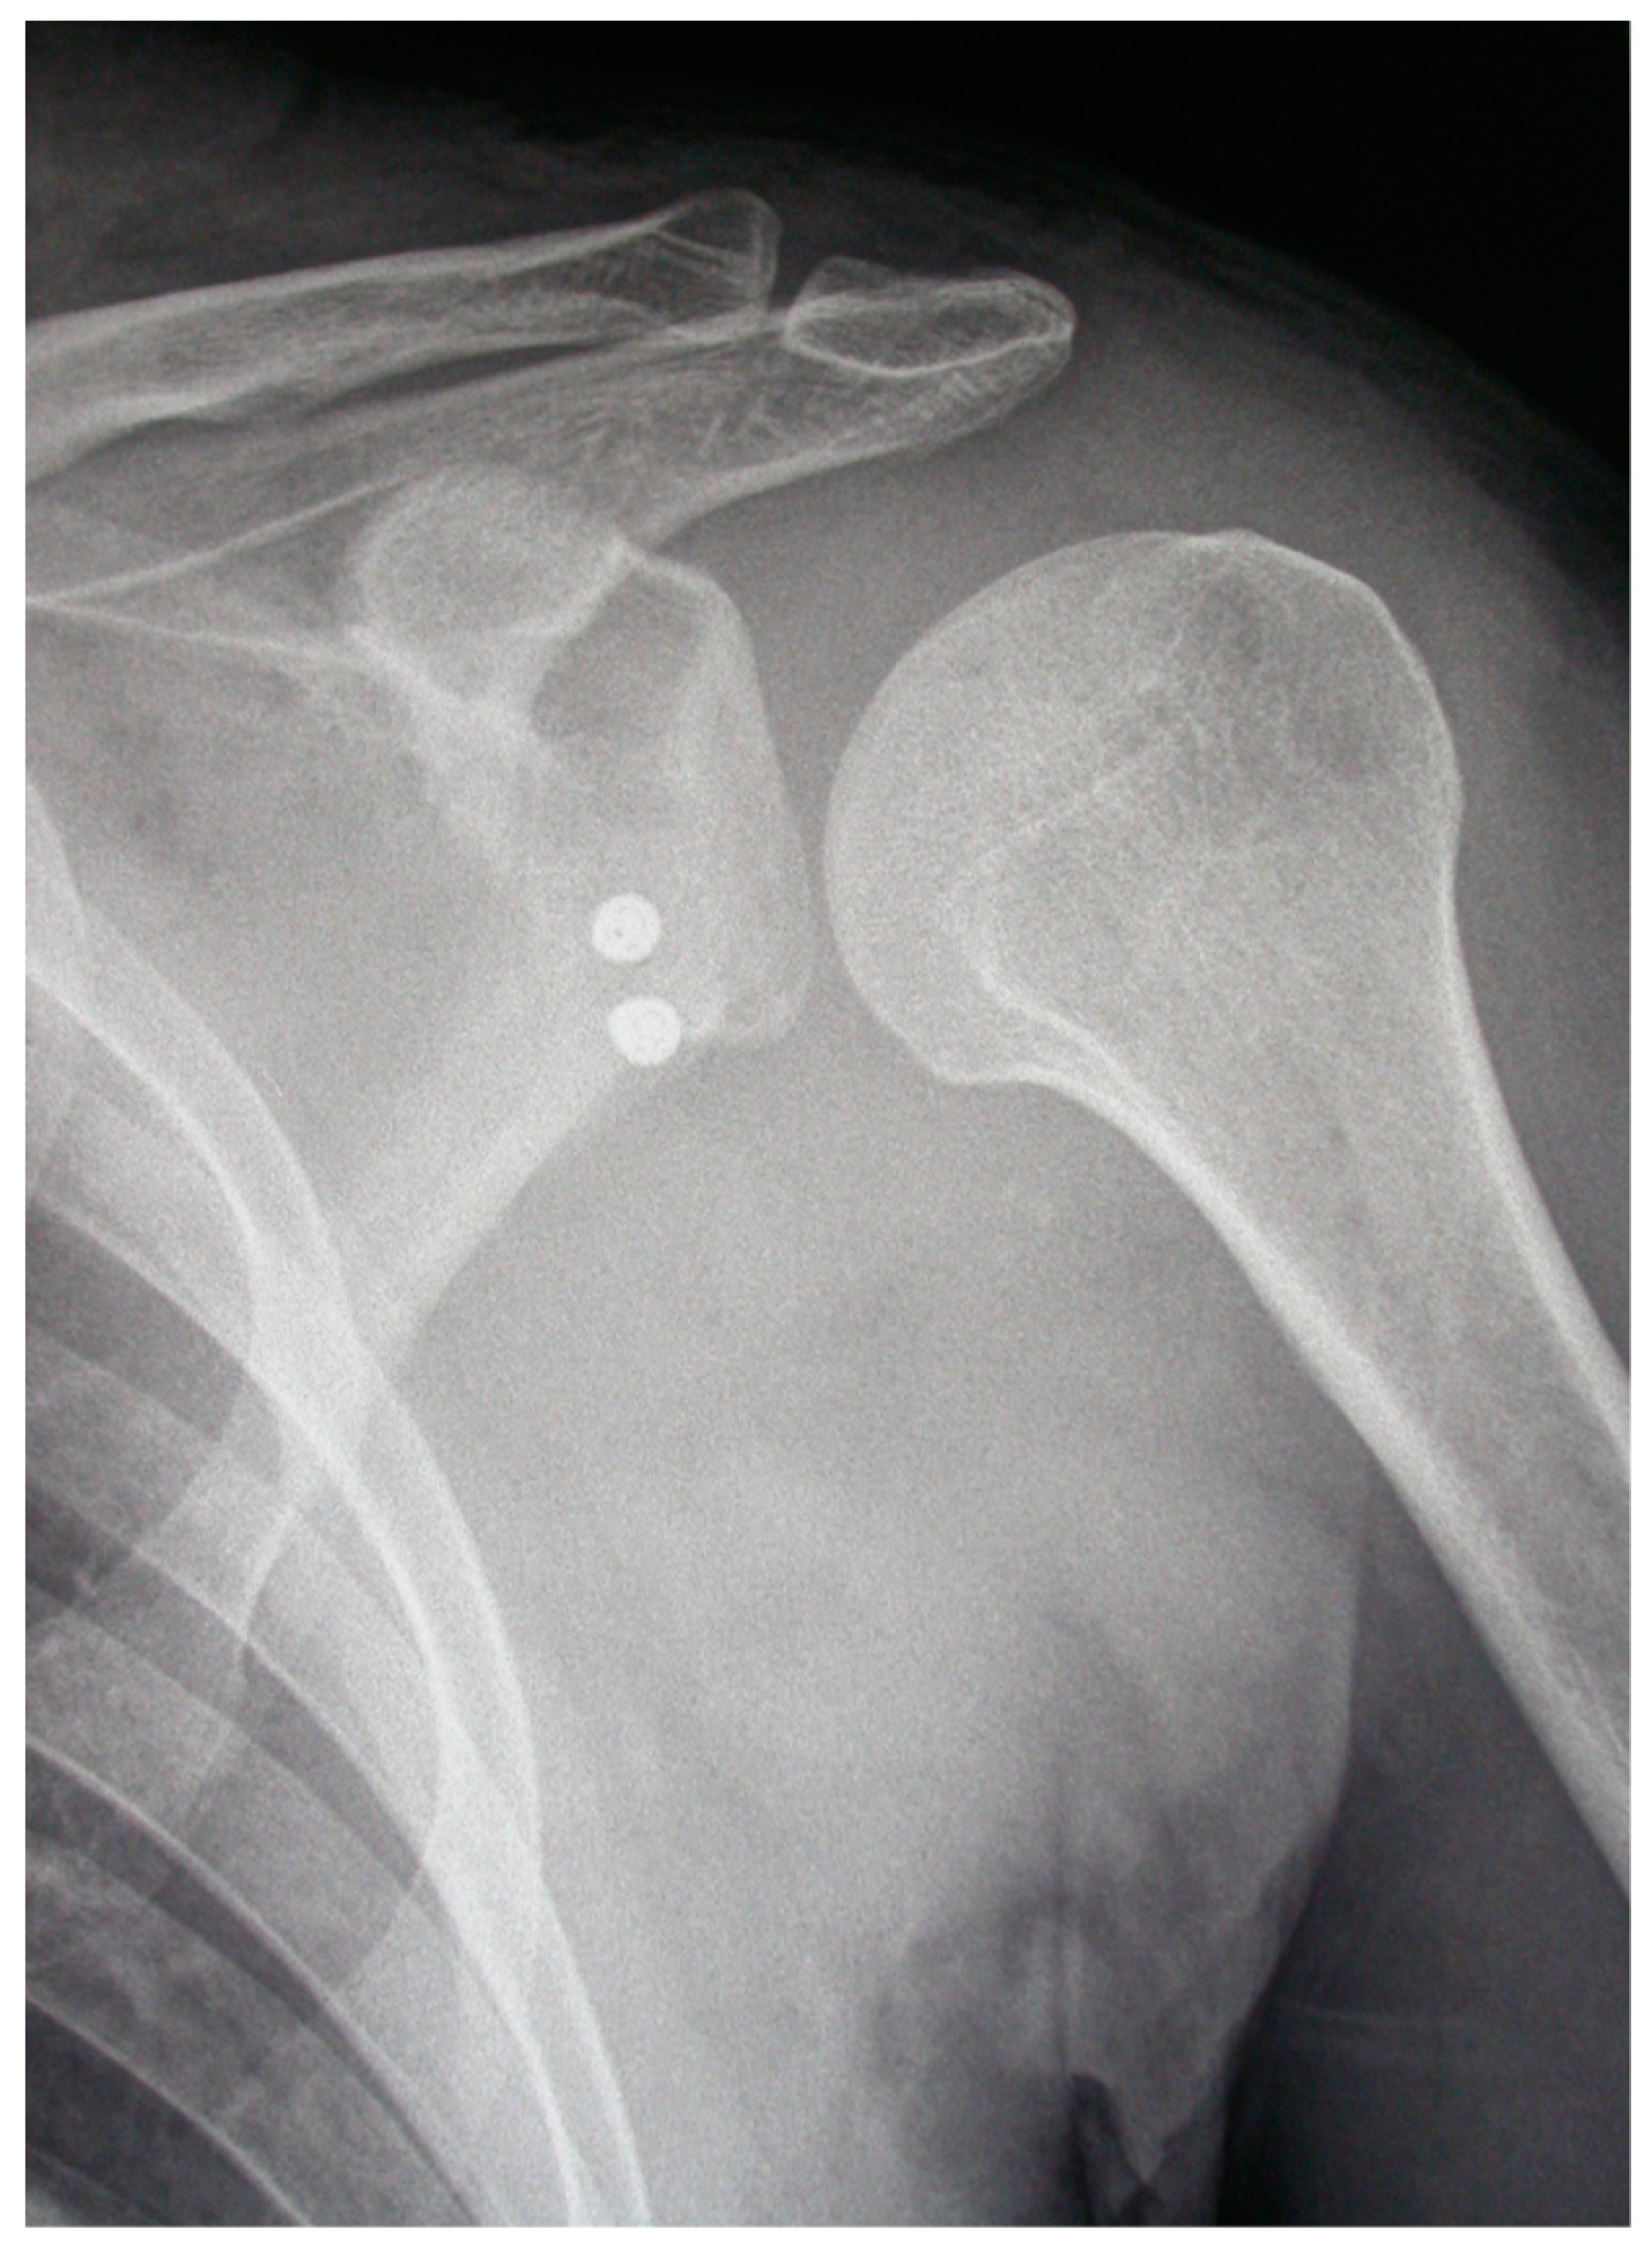

- The pectoralis minor was released, and a fresh portal was established with a needle over the coracoid, to insert the drill holes, at the junction of the lateral 2/3 and the medial 1/3. Two Kirschner wires through the coracoid were passed. The drill guide was removed. The holes were tapped, and the top hats were inserted into the fragment using a flexible Chia wire. The osteotomy was completed (Figure 2). The bone fragment was secured thought a coracoid screw passed over the Chia wire, using a double cannula.